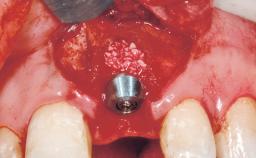

Bone Augmentation Horizontal|Staged

Augmentation Materials Xenogenous|Membrane

Bone Volume Deficient horizontally, requiring prior grafting

Soft Tissue Grafting Simultaneous